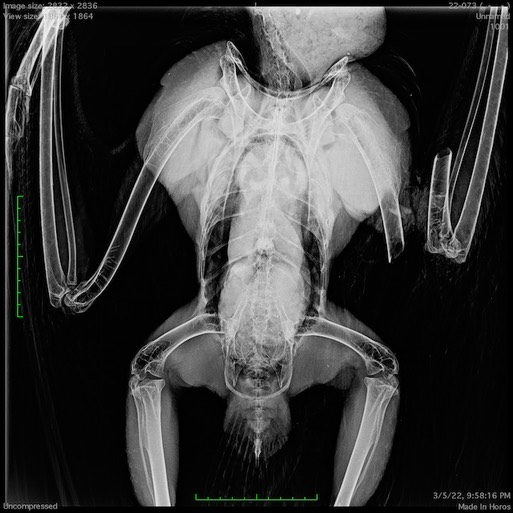

Bald Eagle 22-073

The week ended on a sad note with the admission of an adult bald eagle. The eagle was rescued as it was floating down the Grand Ronde River near Starkey (halfway between Pendleton and La Grande). The eagle had collided with something (a vehicle or power line perhaps) fracturing her right humerus and then fallen into the water. The wing was too badly damaged to repair and the eagle was euthanized.